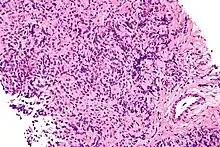

| Micrograph of a primary mediastinal large B-cell lymphoma, a type of large-cell lymphoma. H&E stain. | |

The large-cell lymphomas have large cells. One classification system for lymphomas divides the diseases according to the size of the white blood cells that have turned cancerous. A large cell, in this context, has a diameter of 17 to 20 μm.[1] Other groups of lymphomas in this system are the small-cell lymphomas and mixed-cell lymphomas.